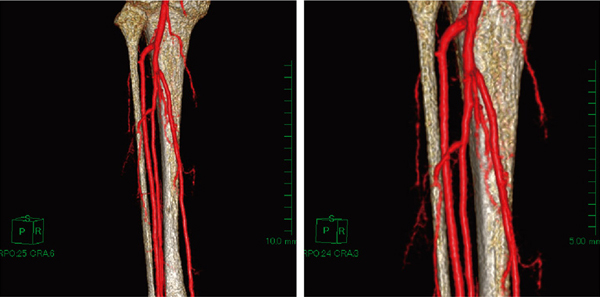

骨の形態情報は,T1強調像の骨髄信号が高信号を呈するという事実から,抽出機能を用いて骨(骨髄)のVR像(volume rendering)を作成し(図6),差分画像の動脈のVR像とマルチボリューム表示することで,MRAの弱点である骨との位置関係が明瞭となった(図7,8)。マルチボリューム表示によって,腓骨,筋肉の切除範囲の決定するための臨床的有用性の高い情報が提供できた。

図7 症例2:下腿部の動脈と骨をマルチボリューム表示したVR像

図8 症例2:下腿部の動脈のVR像

皮膚の情報を付加することによって,外観からの位置を同定するのに有益である。